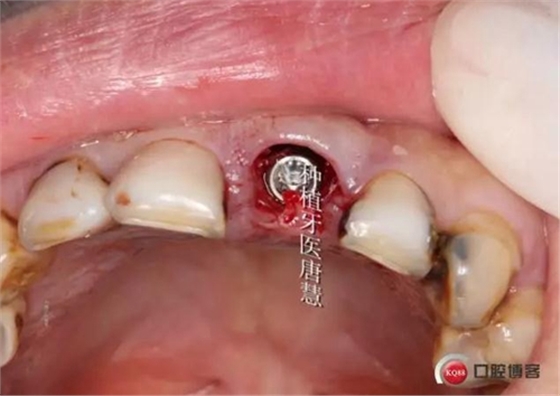

植入植體

植體位于腭側(cè)骨緣下1mm

制作個(gè)性化臨時(shí)基臺(tái)